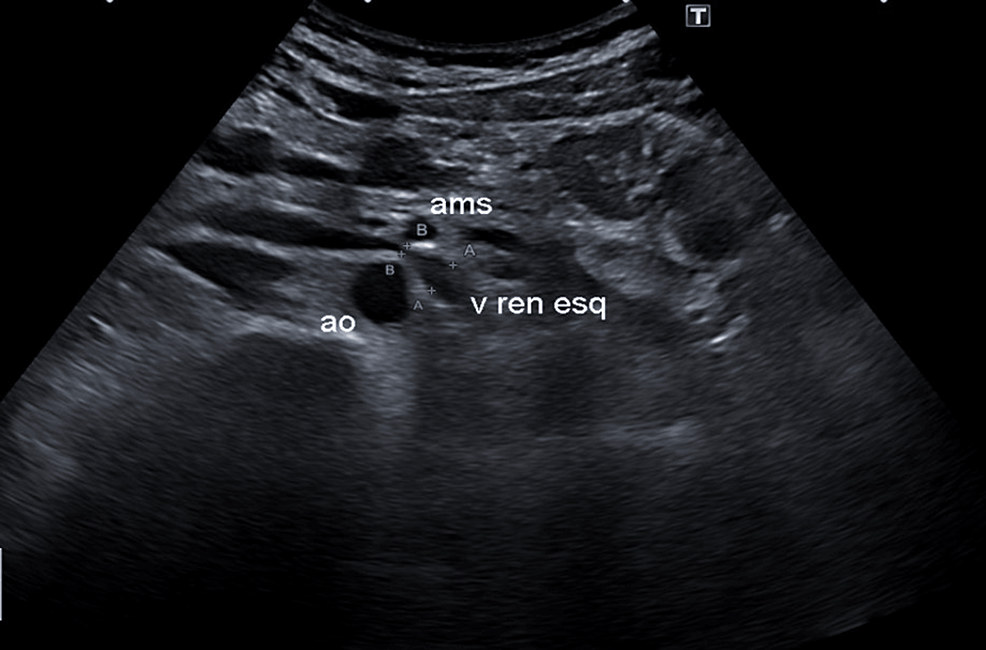

From sonographictendencies.com

Nutcracker Phenomenon/Syndrome Sonographic Tendencies Nutcracker Syndrome Pain Nutcracker syndrome (ns) is a condition in which the left renal vein becomes compressed. Patients most commonly present with unexplained hematuria and flank or pelvic pain, which can be severe at times. Symptoms can worsen with physical activity. The increased left renal vein pressure can lead to left flank pain and gross. This can restrict blood flow, which may lead. Nutcracker Syndrome Pain.